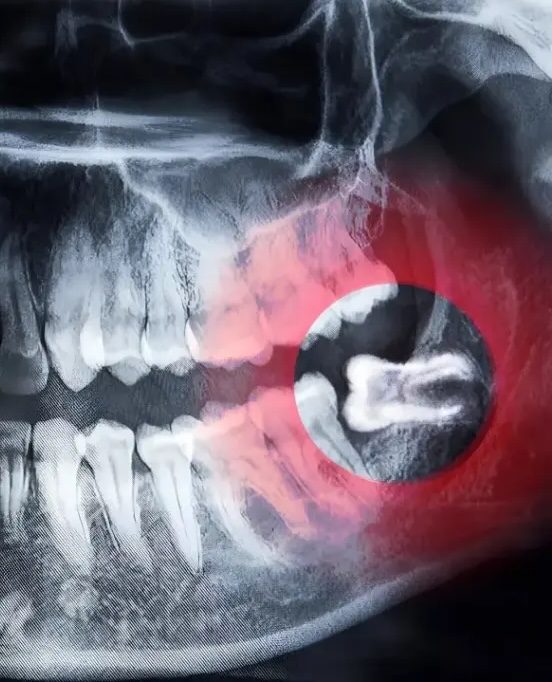

Dental X-ray showing an impacted lower wisdom tooth pressing against the adjacent molar

Panoramic dental X-ray showing an impacted lower wisdom tooth pressing against the adjacent molar

Wisdom teeth often cause problems because they do not fully erupt or come in at improper angles. When this happens, they can trap bacteria and debris beneath the gums.

Some wisdom teeth are straightforward to remove. Others are more complex due to how deeply they are impacted, how the roots formed, or how close they are to nerves.

We use CBCT imaging to evaluate tooth position, root anatomy, and proximity to important structures before planning removal.